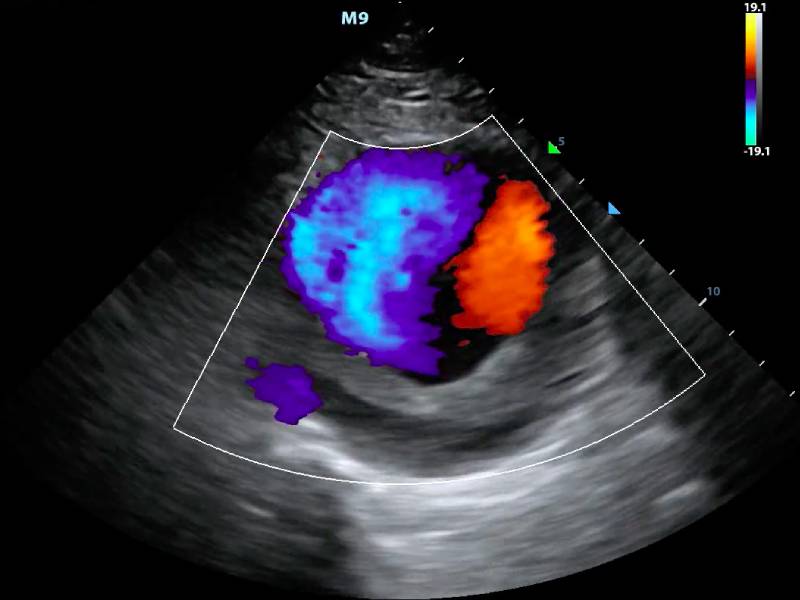

The Colour Doppler Scan, a non-invasive imaging procedure, is a breakthrough in medical diagnostics. It vividly depicts blood flow through veins and arteries, providing critical insights into cardiovascular health. For individuals like Meera, who are constantly on the go and often neglect regular check-ups, this scan offers a comprehensive evaluation without the need for invasive procedures. It is a beacon of hope, promising clarity in the face of uncertainty.

This advanced imaging technique plays a pivotal role in early detection, particularly for conditions like deep vein thrombosis and peripheral artery disease. By providing detailed images of blood flow, it empowers healthcare professionals to diagnose and treat conditions early, preventing complications. For Meera and Rajesh, the scan was more than just a medical procedure; it was a step toward peace of mind.